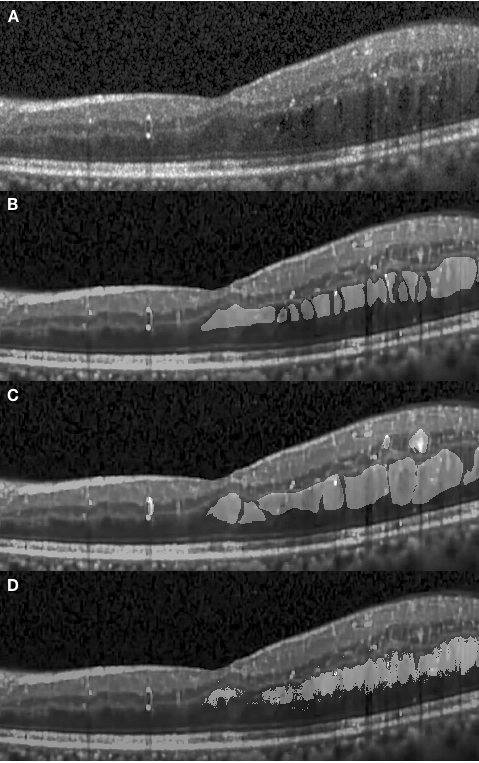

An example of an OCT retinal image exhibiting DME is shown in Fig. 2.1. The retinal layers are deformed and discrete with large cystic fluid areas embedded within the sub-retinal layers. The diabetic edema can be categorized into types: fluid and concrete. The fluid regions, embedded in various shapes and sizes, contain sparse tissue that exhibits low reflectivity. Therefore the fluid regions in the OCT images are generally shown as dark blocks surrounded by layers with high reflectivity. Conversely, the concrete regions are formed by denser tissue. The concrete area is not easily distinguishable from healthy tissue in these images, resulting in the boundary between healthy and diseased tissue not being clearly shown and segmented. Conventionally, the medical professionals segment the concrete area by subjectively estimating the thickness and delineating the boundary at what might be a reasonable position based on their experience. Therefore, different professionals may produce inconsistent results. Figure 2.2 depicts annotations obtained from two graders (both medical professionals). For example, the delineation of edema does not have a good agreement between the two manually segmented images (B and C). At the end of this article, we will show that the proposed method can objectively outperform manual segmentation in terms of consistency metrics.

Figure 4.2 (A) shows a concrete edema embedded within retinal layers on the right-hand side of the fovea region. The distinctive features of this edema are not visually recognizable in this OCT image due to low contrast within the retinal layers. However the presence of the edema causes a deformation of the retinal layers on the right-hand side, with a corresponding change of the layer interval, making them noticeably thicker than those on left-hand side. It is observed in Fig. 4.2 (D) that the segmented results obtained with our approach presents a high correspondence to the manually segmented results. However, it is worth noting that our approach has segmented several regions which had been represented separately under manual annotation as a single large one.